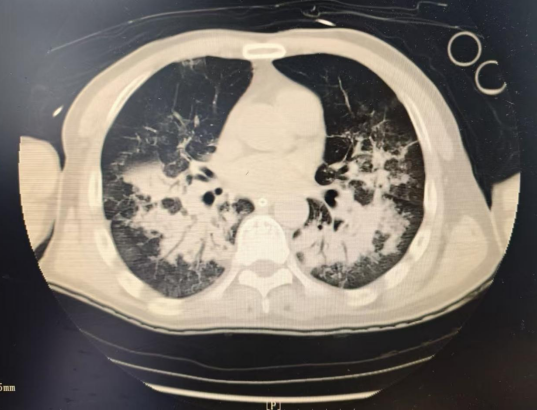

嚴(yán)密監(jiān)護(hù)、及時(shí)調(diào)整治療策略、控制感染、腸內(nèi)營(yíng)養(yǎng)、氣道管理、皮膚管理、心理護(hù)理、預(yù)防并發(fā)癥……經(jīng)過(guò)全科醫(yī)護(hù)人員的不懈努力,20多天驚險(xiǎn)緊張的救治后,從“鬼門(mén)關(guān)”走了一圈的老吳終于化險(xiǎn)為夷,感染得到有效控制,多器官衰竭逐步逆轉(zhuǎn),最終成功脫離呼吸機(jī),順利轉(zhuǎn)入普通病房進(jìn)行后續(xù)治療。

治療后CT影像